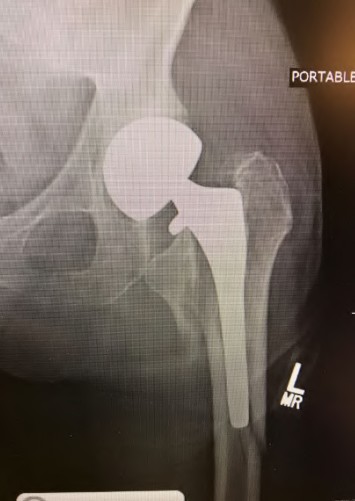

A 72-year-old female presents with progressive left thigh and knee pain for the last year. 5 years ago she sustained a femoral neck fracture treated with the implant seen in Figures A-C (current radiographs). The thigh pain is worse with weight-bearing. C-reactive

protein and erythrocyte sedimentation levels are within defined limits. Which of the following is the most likely cause of her pain?